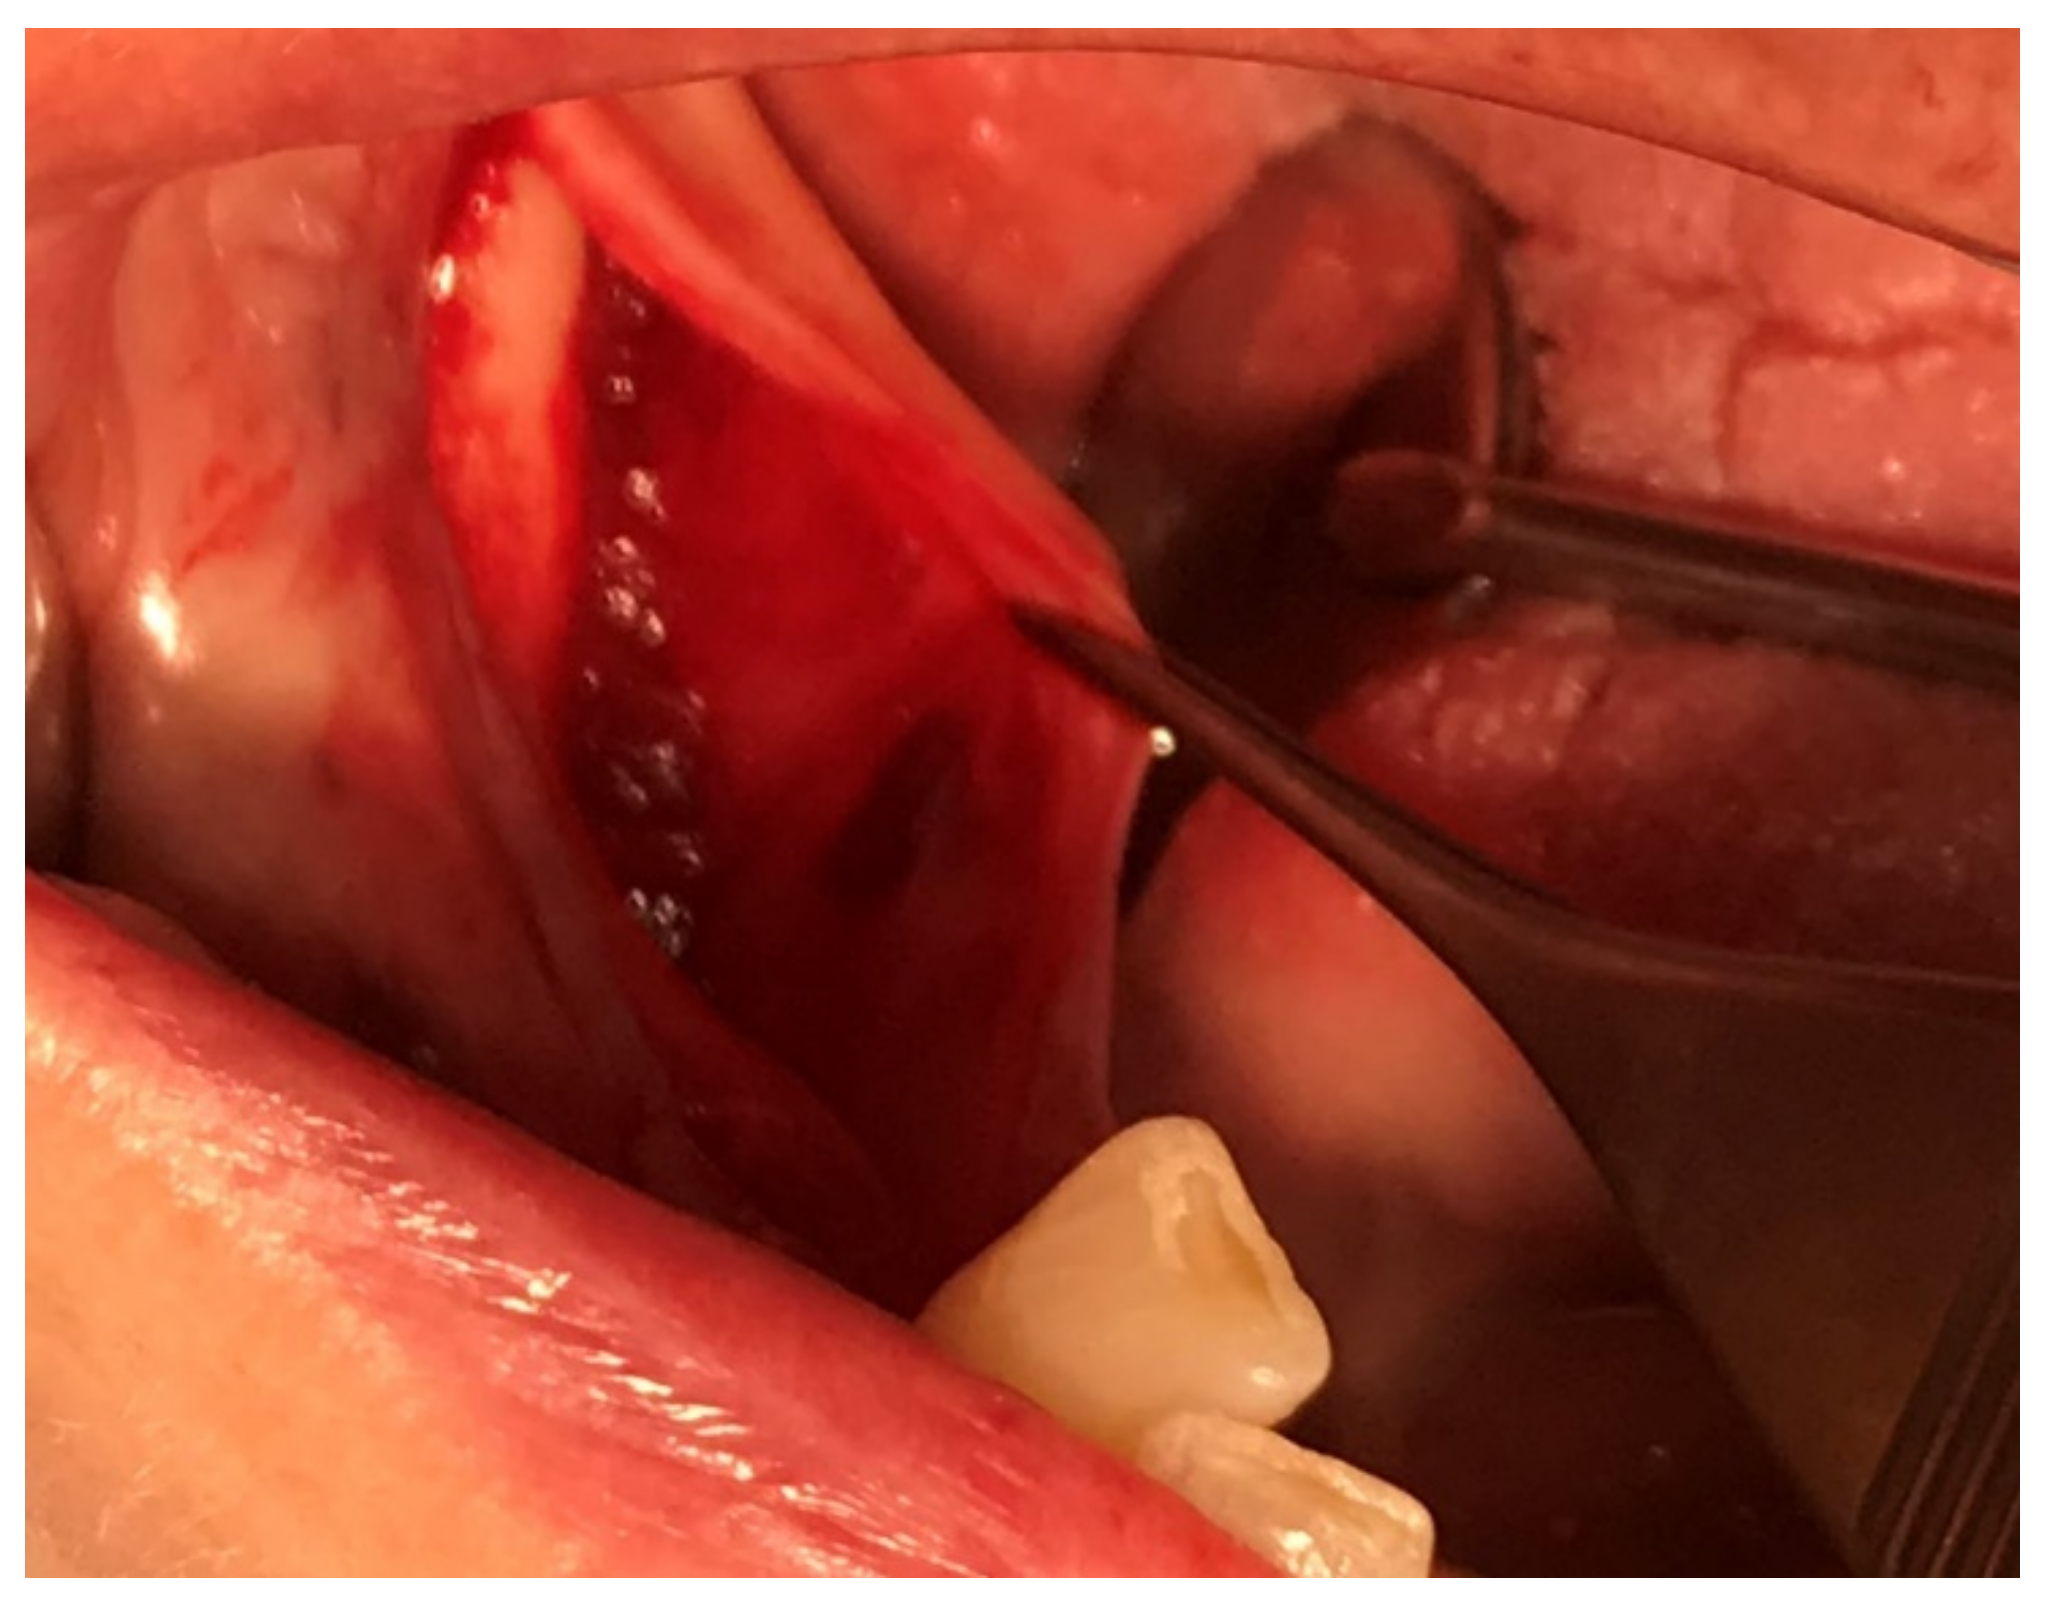

A preoperative systemic antibiotic therapy with 600 mg of clindamycin due to a history of penicillin allergy was initiated one hour before surgery, as well as supplemental pain medication with 600 mg of Ibuprofen. Chlorhexidine mouth rinse was used 60 s before surgery. Under local anesthesia with Articain (Ultracain-DS® forte), a full thickness flap elevation with a crestal incision was performed in the keratinized tissue, from the retromolar pad to the distal surface, of the most distal tooth (#27). No vertical release or elevation by the mylohyoid line was needed to get sufficient elevation of the flap (Figure 5).

Figure 5.

Flap advancement for sufficient cover of the bone block.